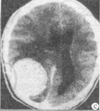

2.(如图所示)首先考虑![]() |

| 正确答案:C 解题思路:环形强化,环内低密度,明显占位效应,考虑脑脓肿。 |